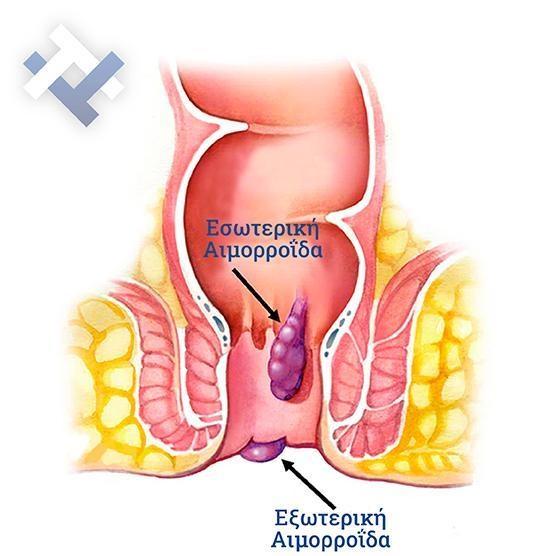

Θεραπεία αιμορροϊδων με laser (LHP)

Αφαίρεση αιμορροΐδων με υπερήχους (HALL-RAR)

Xωρίς χειρουργείο με ελαστικούς δακτυλίους (Τεχνική BARON-RBL)

Ο Γενικός Χειρουργός Λιάγκος Γεώργιος MD PhD εκτελεί τις επεμβάσεις Λαπαροσκοπικά, Ενδοσκοπικά, Ανοιχτά Ελάχιστα Επεμβατικά και με Laser. Η θεραπεία εξατομικεύεται σε κάθε ασθενή ανάλογα με τις ανάγκες του. Αναλαμβάνει περιπτώσεις όπως κήλες και κοιλιοκήλες (αντιμετώπιση βουβωνοκήλης, αντιμετώπιση ομφαλοκήλης, θεραπεία επιγαστρικής κήλης, κήλη των αθλητών (Σύνδρομο κοιλιακών προσαγωγών), αντιμετώπιση μετεγχειρητικής κήλης, θεραπεία Μηροκήλης), πέτρες στη χοληδόχο κύστη, λαπαροσκοπική χολοκυστεκτομή, αντιμετώπιση Κύστη Κόκκυγος με λέιζερ (laser), παθήσεις πρωκτού, χειρουργική laser σύγχρονων κυκλικών ινών (αιμορροΐδες αντιμετώπιση, θεραπεία αιμορροϊδων με laser (LHP), αφαίρεση αιμορροΐδων με υπερήχους (HALL-RAR), χωρίς Χειρουργείο με ελαστικούς δακτυλίους (Τεχνική BARON-RBL), θεραπεία ραγάδας πρωκτού (Ραγάδα δακτυλίου), θεραπεία περιεδρικού συριγγίου, θεραπεία περιεδρικού αποστήματος, κονδυλώματα πρωκτού Θεραπεία, δερματικό ράκος (Skin tag) εκτομή, αντιμετώπιση Kνησμού, καρκίνος πρωκτού θεραπεία), παθήσεις Δέρματος, χειρουργική με laser CO2, αφαίρεση μορφωμάτων δέρματος - βιοψίες, αφαίρεση ελιάς (Σπίλου), σμηγματογόνος κύστης θεραπεία, αφαίρεση λιπώματος, είσφρυση όνυχος χειρουργείο, καρκίνος δέρματος θεραπεία, οξεία σκωληκοειδίτιδα, παθήσεις Λεπτού και Παχέος Εντέρου, ειλεός λεπτού εντέρου, εκκολπωμάτωση (Εκκολπωματίτιδα) σιγμοειδούς, καρκίνος παχέος εντέου, κολοστομίες, port χημειοθεραπείας κ.α. εξυπηρετώντας Παγκράτι και γύρω περιοχές.